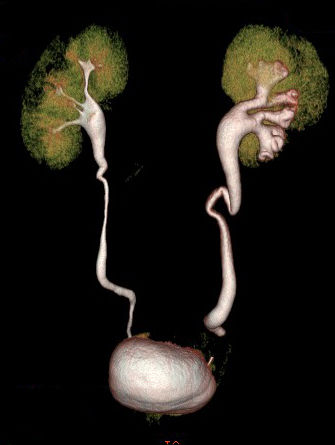

TC DE ABDOMEN Y PELVIS

Es una radiografia tomada de manera continua. Entrega detalle antaomico muy superior a la radiografia simple. Permite evaluar lesiones menores de 1 mm. El problema es que se irradia al paciente y se usa medio de contraste que úede afectar a la funcion renal. Pielo TC: No usa medio de contraste. Para ver litiasis especificamente, menos de 700 unidades de desnisas son calculos radiolucidos como los de acido urico. Permite determinar carga litiasica, localizacion , densidad, signos secundarios( inflamacion, dilatacion. compromiso pre renal) y el pronostico TC de abdomen y pelvis siempre es con contraste y permite determinar carga litiasica, progrmar citugia, evaluar que via utilizar. Permite caracterizar masa renales, suprarrenales, infecciones de tracto urinario como PN complicada, hidropionefrosis, absceso renal, absceso perinefritico, alteraciones anatomicas de via urinaria superior, etapificacion de neoplasia riñon y suprarrenales, trauma urnario El hueso se ve blanco y el aire o agua se ve negro. Se evlua a traves de densidad tomografica de Hounsfield

Uro TC:  Tiene una fase sin contraste como el pieloTC, fase corticomedular que dura 40 minutos, donde se ven lesiones del parenquima y se ven bien definidos los riñones, luego la afase nefrogenica donde se impregana las masas renales y por ultimo la fase tardia o excretora, donde se ve bien dibujado el sistema urinario. Sirve para ver lesiones de urotelio que midan menos de 5 mm. En estudio de hematurio se utiliza cistografia y Uro TC. Lesiones de urotelio superior, rotura de via excretora, lesiones de vejiga.